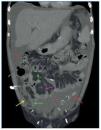

Figura 1.Tomografía computarizada abdominopélvica tras administración de contraste intravenoso, corte axial a nivel de mesogastrio. Se observa un engrosamiento difuso del peritoneo parietal y visceral (flecha amarilla), calcificaciones en forma de pequeñas placas del peritoneo parietal (flecha roja), calcificaciones «en sábana» del peritoneo visceral (flecha verde), asas de intestino delgado de localización central y de diámetro intraluminal disminuido (asteriscos amarillos) y ascitis loculada en ambas gotieras paracólicas (asteriscos rojos) de predominio derecho. Nótese cómo la ascitis loculada desplaza medialmente a las asas de intestino delgado y grueso.

Los signos radiológicos de la PE se pueden dividir en tres categorías: anomalías del peritoneo, anomalías en las asas de intestino delgado y la presencia de colecciones líquidas o ascitis loculada3.

La afectación del peritoneo se caracteriza por un engrosamiento de este primero en forma de placas aisladas y más tarde difuso, afectando tanto a la capa de peritoneo visceral como a la parietal3 (figuras 1 y 3). En los estudios de TC realizados tras la administración de contraste intravenoso se puede observar el realce aumentado del peritoneo engrosado2 (figura 3). Las calcificaciones que se producen en el peritoneo comienzan siendo lineales, como pequeñas placas, y evolucionan a calcificaciones «en sábana» (figuras 1-4) y en forma de conglomerados2,3 (figura 4).

Las asas de intestino delgado aparecen engrosadas, con una disminución de su diámetro intraluminal (figuras 1, 3 y 4) y de localización central. También se pueden observar calcificaciones de sus paredes. Como resultado de las membranas fibróticas que se desarrollan envolviéndolas (figuras 2, 3 y 4), la raíz del mesenterio se retrae y se origina un conjunto de adherencias internas, que pueden causar una obstrucción de intestino delgado. En este último caso, las asas se mostrarán dilatadas y como complicación se puede producir necrosis y perforación de estas2,3.

Los pacientes con DP inevitablemente tendrán ascitis3 y, debido al engrosamiento y la fibrosis de las membranas peritoneales, será una ascitis loculada (figuras 1, 2, 3 y 4), que contribuye a la distribución central de las asas de intestino delgado3.